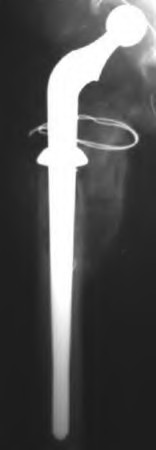

Question 32

A 45-year-old female with developmental dysplasia of the hip (DDH) presents for THA. Preoperative radiographs show the femoral head is subluxated, with 80% proximal migration relative to the height of the normal true acetabulum. Based on the Crowe classification, what type of dysplasia does she have?

Explanation